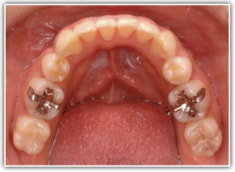

治療後(2年後)